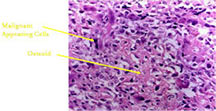

- Tumor has cyst-like spaces divided by septa

- Septa composed of atypical, bizarre, malignant appearing spindle cells with atypical nuclei and atypical mitotic figures

- Osteoid production is scant, focal and lace-like

- High degree of nuclear atypia, cellular pleomorphism, normal and atypical mitotic activity

- In highly necrotic tumors that appear grossly as blood clot, malignant cells may be separated in a background of necrotic and bloody debris and may be difficult to identify.